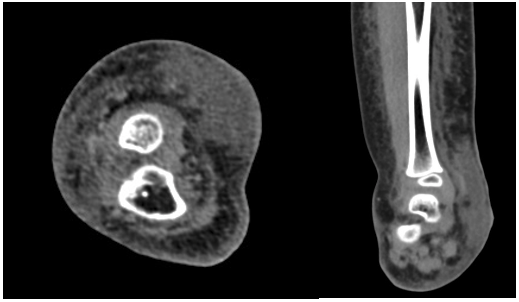

A 4-year-old boy presented to the clinic 2 years ago with well-defined, hyperkeratotic, erythematous plaques in a linear pattern over the medial aspect of his right tibia, extending to his ankle. These lesions were present at birth as flat, pink macules that were initially identified as a port wine stain (Figure 1). The initial treatment was with a pulsed dye laser (595-nm wavelength), but it did not respond. The macules grew hyperkeratotic and verrucous over time (Figure 2). Oral propranolol (20 mg bid) was initiated to no avail. Sonographic assessment of the medial aspect of the right ankle showed a widening of the subcutaneous space with amorphous, hyperechoic lesions without any significant internal flow (Figure 3). Further contrast-enhanced computed tomography shows skin thickening and soft tissue density at the medial aspect of the right ankle in the dermal and subcutaneous space (Figure 4). Additional magnetic resonance imaging (MRI) from March 2020 to evaluate superimposed cellulitis showed a 3.5 × 1.1 × 4.3-cm T1 intermediate, T2 hyperintense mass confined to the subcutaneous soft tissue along the medial aspect of the ankle along with extensive subcutaneous edema (Figure 5). The lesions were biopsied and positive for GLUT1 and a diagnosis of VVM was made. During his results at 1 year, a surgical approach was chosen. However, due to the location in the distal third of the lower leg involving the ankle, complete extirpation was not possible without necessitating a complex reconstruction (Figure 6). The lesions were partially excised to a depth of normal-appearing subcutaneous tissue. The resultant wounds were closed primarily. Our patient recovered well and healed without complications.

Figure 4. Contrast-enhanced computed tomography images (axial and coronal) show skin thickening and widening of the subcutaneous space due to infiltrating soft tissue density.